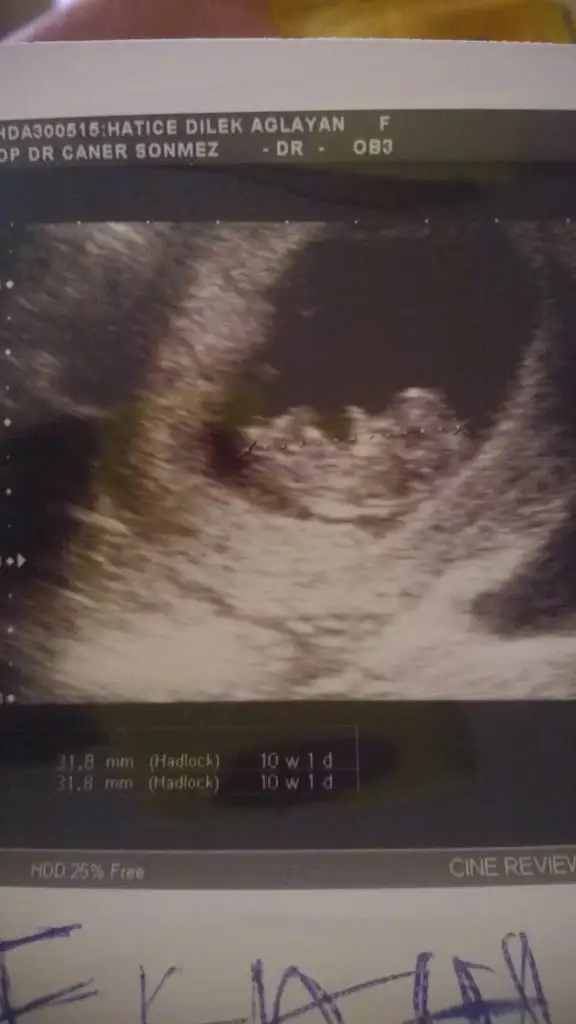

Kizlar bakarmisiniz. Doktor 11hafta 1gunluk diyor ama ben yumurtlama günümü bildiyim Have you send?için 12hafta 2gunluk die hesapladim hep. Resme bakarmisiniz kimdir sizcə bu çocu

k?? Doktor tahmin bilə yapmadi